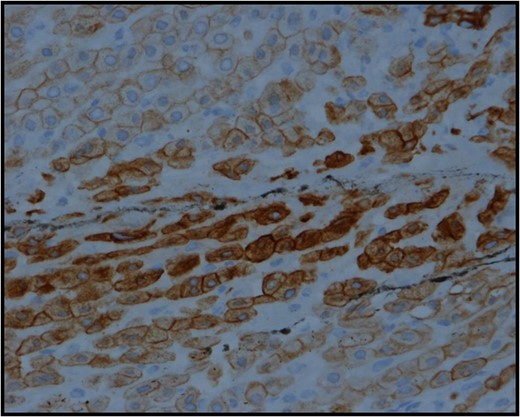

Section from the adrenocortical mass showing strong positive cytoplasmic staining with low molecular weight cytokeratin-cam 5.2 IHC stain.